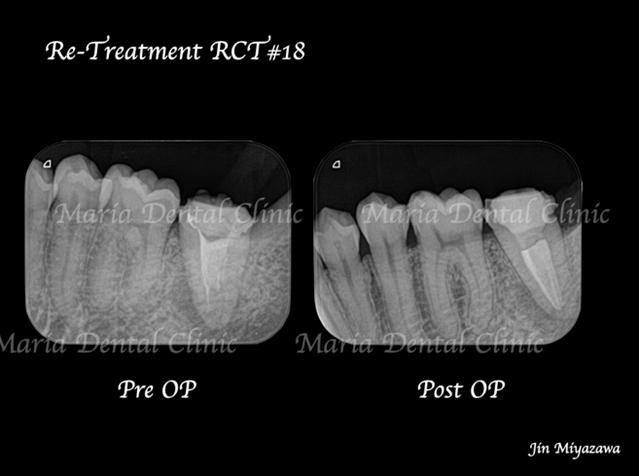

【症例】再根管治療| CT、マイクロスコープを使った精密根管治療